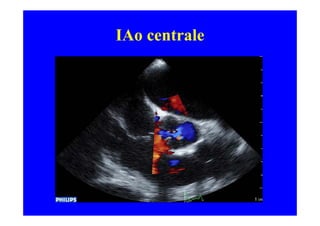

Défaut de coaptation central en

ETO

• Diastole         Systole

Défaut de coaptation central

IAo centrale